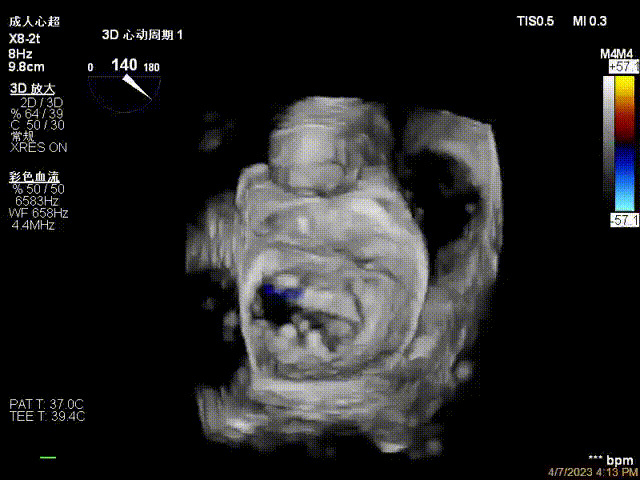

接受治療的是一例器質性重度二尖瓣反流(DMR)患者,主訴“反復活動后胸悶,氣促3年余”。術前超聲顯示,雙房增大,二尖瓣脫垂伴重度反流,輕度三尖瓣反流,輕度肺高壓,升主動脈增寬。手術經股靜脈-房間隔入路,采用全身麻醉插管,在TEE和DSA引導下完成房間隔穿刺。置入JensClip瓣膜夾系統后,在左房調整瓣膜夾的位置和軸向,后進入左室,在TEE引導下捕捉二尖瓣前后瓣葉,并關閉瓣膜夾。經TEE反復確認手術效果后最終鎖定并釋放瓣膜夾。術后即刻超聲顯示瓣膜夾位置穩定,功能良好,術前二尖瓣反流4+,術后0反流,肺靜脈逆流和左房壓都顯著好轉,手術圓滿成功(以上數據都來源于醫院的臨床記錄)。術后患者狀態良好,目前已安排出院。

術后超聲顯示二尖瓣反流消失,瓣膜夾穩定